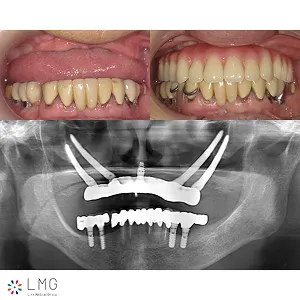

下顎オールオンフォー、上顎ザイゴマインプラント 「ザイゴマインプラント治療」を行われた患者さまのビフォーアフターをご紹介します。 ※ご紹介している症例は、あくまでも患者様固有の症例ですので、実際には患者様によって治療期間 […]